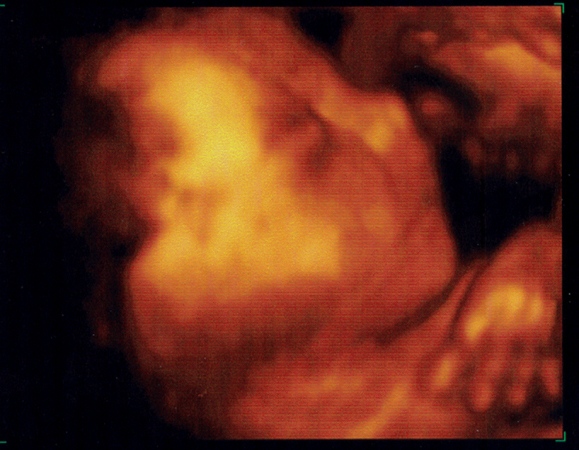

A genesis szerintem nagyon jó kis rendelő. Kedvesek és nem túl drága. Velem pl nagyon készségesek voltak annak idején, majd 1,5 órát ultrahangoztak, hogy egyaltalán profilból lássuk a gyereket.... mert máshogy sehogysem sikerült.

Teszek fel egy ilyen volt ilyen lett képet!